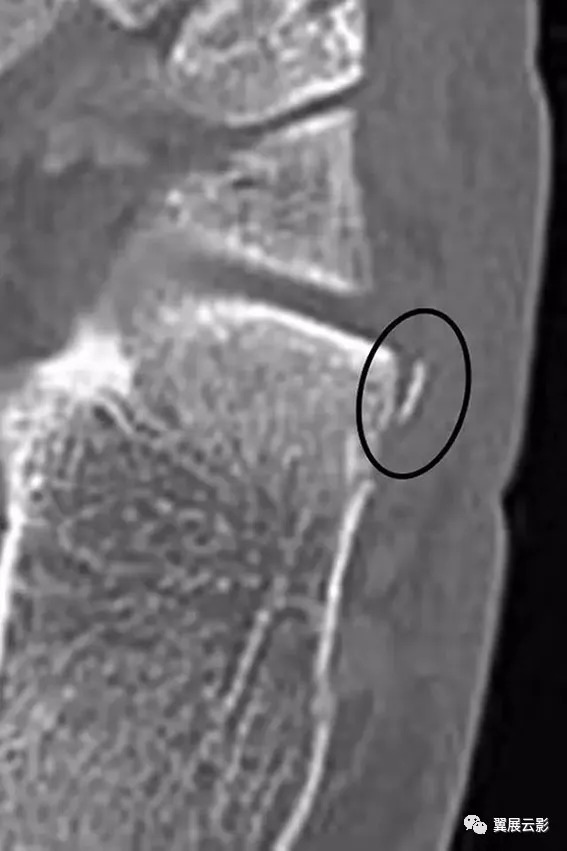

图10A -21岁的男性篮球运动员,脚外侧疼痛。A,脚的倾斜视图的特写镜头显示线性骨头(箭头)接近跟骰关节。

图10B- CT图像显示撕脱性骨折(椭圆形)对应于背侧跟骨韧带的近端附着。